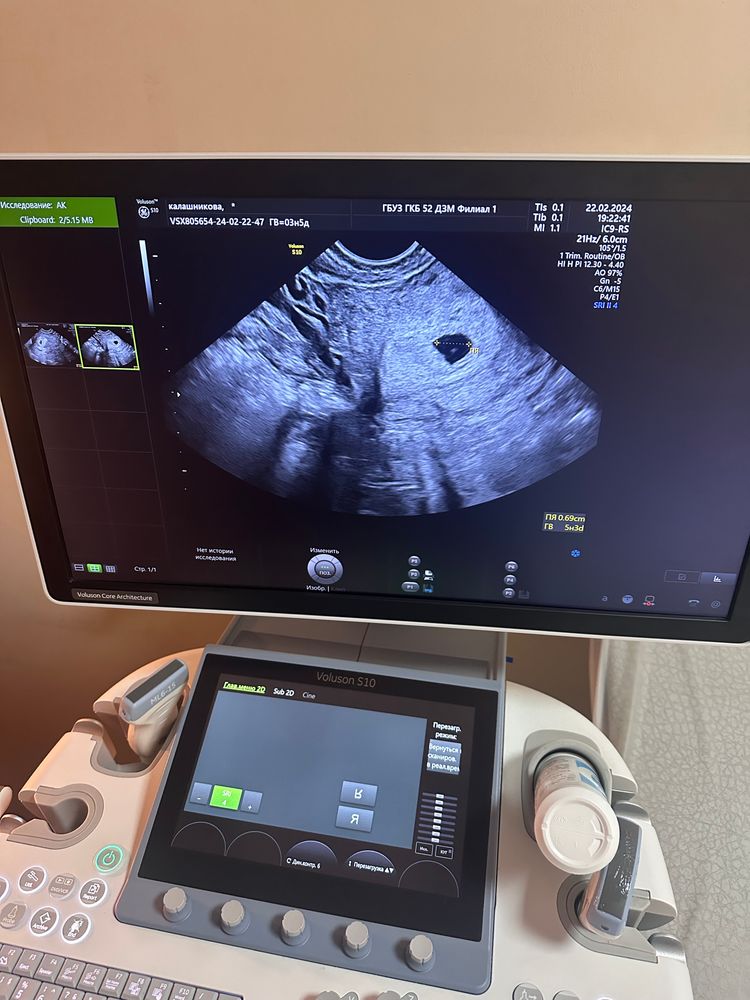

22.02 сходила на , подтвердили маточную беременность. Увидели 1 ПЯ размером 6 мм, желточный мешок 1,5 мм. Срок по узи 5 недель, 3 дня.